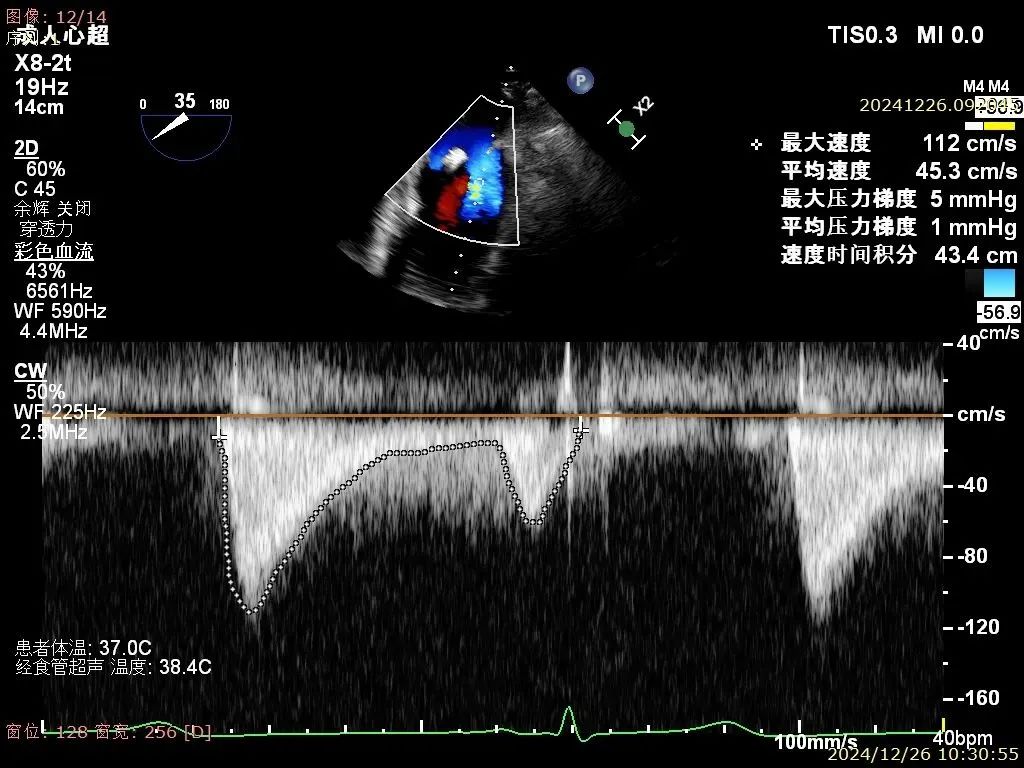

患者为68岁男性,3月前出现气短,活动后明显,休息可缓解,无明显胸痛,无夜间呼吸困难,就诊当地医院考虑“肺炎、心衰”,给予对症治疗好转,具体不详,无明显发热,无咳嗽咳痰,出院后未规律服药。10天前,气短再发,就诊当地医院心脏彩超提示二尖瓣后叶腱索断裂,二尖瓣关闭不全伴重度反流。左心增大,室间隔增厚,肺动脉高压,三尖瓣轻度反流,主动脉瓣中度反流。心电图提示房颤,左室肥大。为进一步诊治入院。经食道超声提示:患者二尖瓣后叶脱垂伴腱索断裂,前叶2.6cm,后叶1.4cm,脱垂宽度16mm,脱垂高度8mm,瓣口面积6.0cm²。

术前影像

二尖瓣夹释放后评估